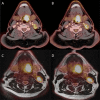

Reproducibility of (18)F-FDG PET uptake measurements in head and neck squamous cell carcinoma on both PET/CT and PET/MR

Objective: To investigate reproducibility of fluorine-18 fludeoxyglucose ((18)F-FDG) uptake on (18)F-FDG positron emission tomography (PET)/CT and (18)F-FDG PET/MR scans in patients with head and neck squamous cell carcinoma (HNSCC).

Methods: 30 patients with HNSCC were included in this prospective study. The patients were scanned twice before radiotherapy treatment with both PET/CT and PET/MR. Patients were scanned on the same scanners, 3 days apart and according to the same protocol. Metabolic tumour activity was measured by the maximum and peak standardized uptake value (SUVmax and SUVpeak, respectively), and total lesion glycolysis from the metabolic tumour volume defined from ≥50% SUVmax. Bland-Altman analysis with limits of agreement, coefficient of variation (CV) from the two modalities were performed in order to test the reproducibility. Furthermore, CVs from SUVmax and SUVpeak were compared. The area under the curve from cumulative SUV-volume histograms were measured and tested for reproducibility of the distribution of (18)F-FDG uptake.

Results: 24 patients had two pre-treatment PET/CT scans and 21 patients had two pre-treatment PET/MR scans available for further analyses. Mean difference for SUVmax, peak and mean was approximately 4% for PET/CT and 3% for PET/MR, with 95% limits of agreement less than ±20%. CV was small (5-7%) for both modalities. There was no significant difference in CVs between PET/CT and PET/MR (p = 0.31). SUVmax was not more reproducible than SUVpeak (p = 0.09).

Conclusion: (18)F-FDG uptake in PET/CT and PET/MR is highly reproducible and we found no difference in reproducibility between PET/CT and PET/MR.